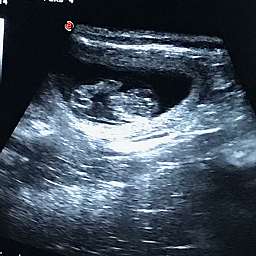

12.6.2018, 30.Tag: Um 11.00Uhr startete unser großer Moment: Adeles Wunder wurde von unserer Tierärztin geschallt.

Wir sind überglücklich Euch mitteilen zu dürfen, daß Adele tragend ist. Beim Ultraschall sahen wir völlig überwältigt 4 - 5 kleine Fruchthüllen mit pochenden Herzen darin.

19.00Uhr: Adele liegt in der Wurfbox und hechelt. Schon über den ganzen Tag hat sie immer wieder Wehen. Auf dem Ultraschallbild war zu sehen, daß 2 der Welpen in Kopflage schon recht weit Richtung Ausgang liegen. Der Rest liegt kreuz und quer. Wir dürfen gespannt sein...